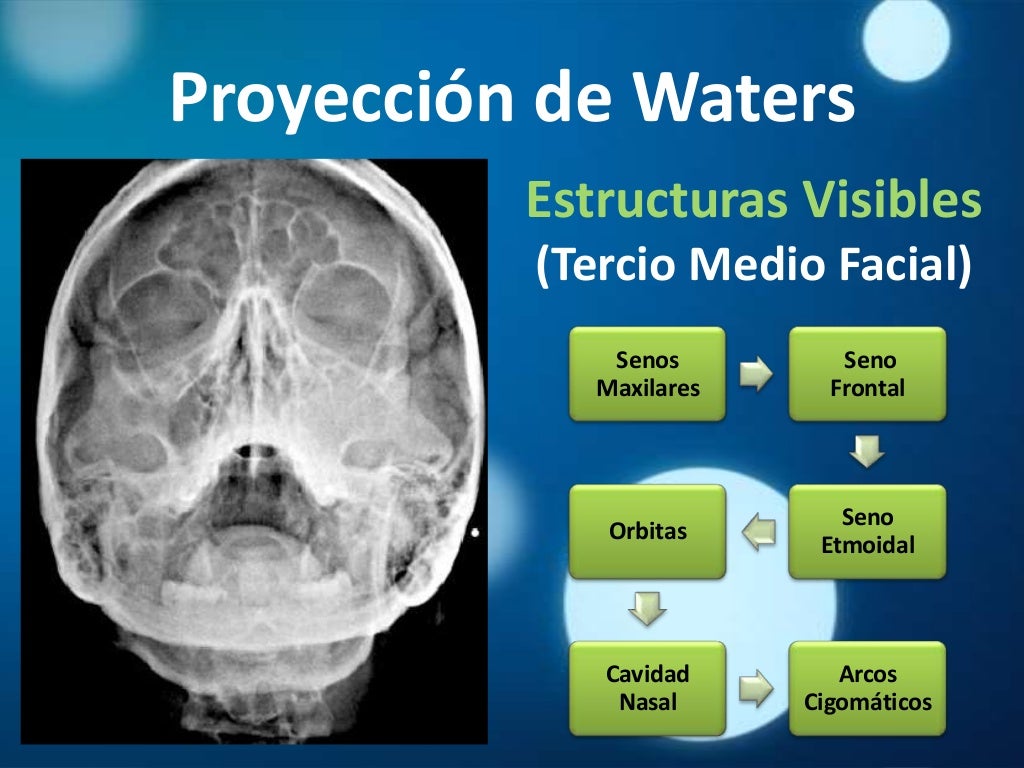

Download scientific diagram | Proyección de Waters: aumento de densidad de partes blandas de los senos maxilares (estrella) y presencia de masa en la faringe (flecha). from publication: Pólipo.. Citation, DOI, disclosures and article data. The Caldwell view is a caudally angled radiograph, with its posteroanterior projection allowing for minimal radiation to the orbits. This view may be used in imaging of the skull or facial bones depending on the clinical indications.

¿Dónde se encuentra el seno esfenoidal en una radiografía de cráneo en proyección de Waters

Dx por imagen Craneo Columna RADIOGRAFIA DE CRANEO Proyección de Waters, esta proyección nos

Waters de Cráneo Orthodiagnóstico

Senos Paranasales Imagenología

Senos paranasales

Senos paranasales

Senos Paranasales Imagenología

Semiologia y radiologia de senos paranasales